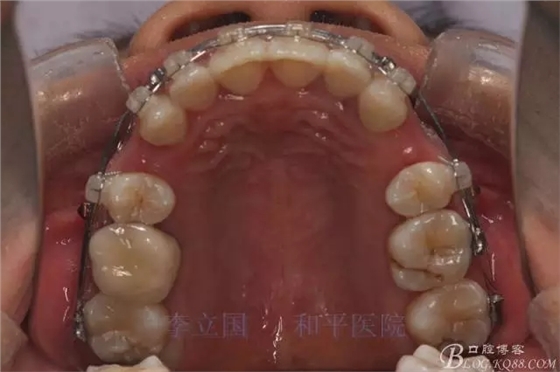

2.Damonclear排齊整平。

3.微種植支抗內(nèi)收上下前牙。

3.上頜應(yīng)用支抗釘。表麻下在56牙槽間隔植入,注意因使用的為鈦合金釘,一直保持植入角度與骨面成60度角,不要垂直植入再改變角度。要求即刻加載,即刻加載力值2盎司。

4.使用長(zhǎng)牽引鉤,使?fàn)恳咏项M骨阻抗中心,防止上頜骨的順時(shí)針旋轉(zhuǎn)。